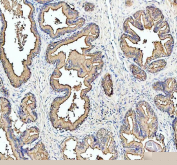

IHC staining of FFPE human prostate cancer tissue with MARS1 antibody, HRP-labeled secondary and DAB substrate. HIER: boil tissue sections in pH8 EDTA for 20 min and allow to cool before testing.